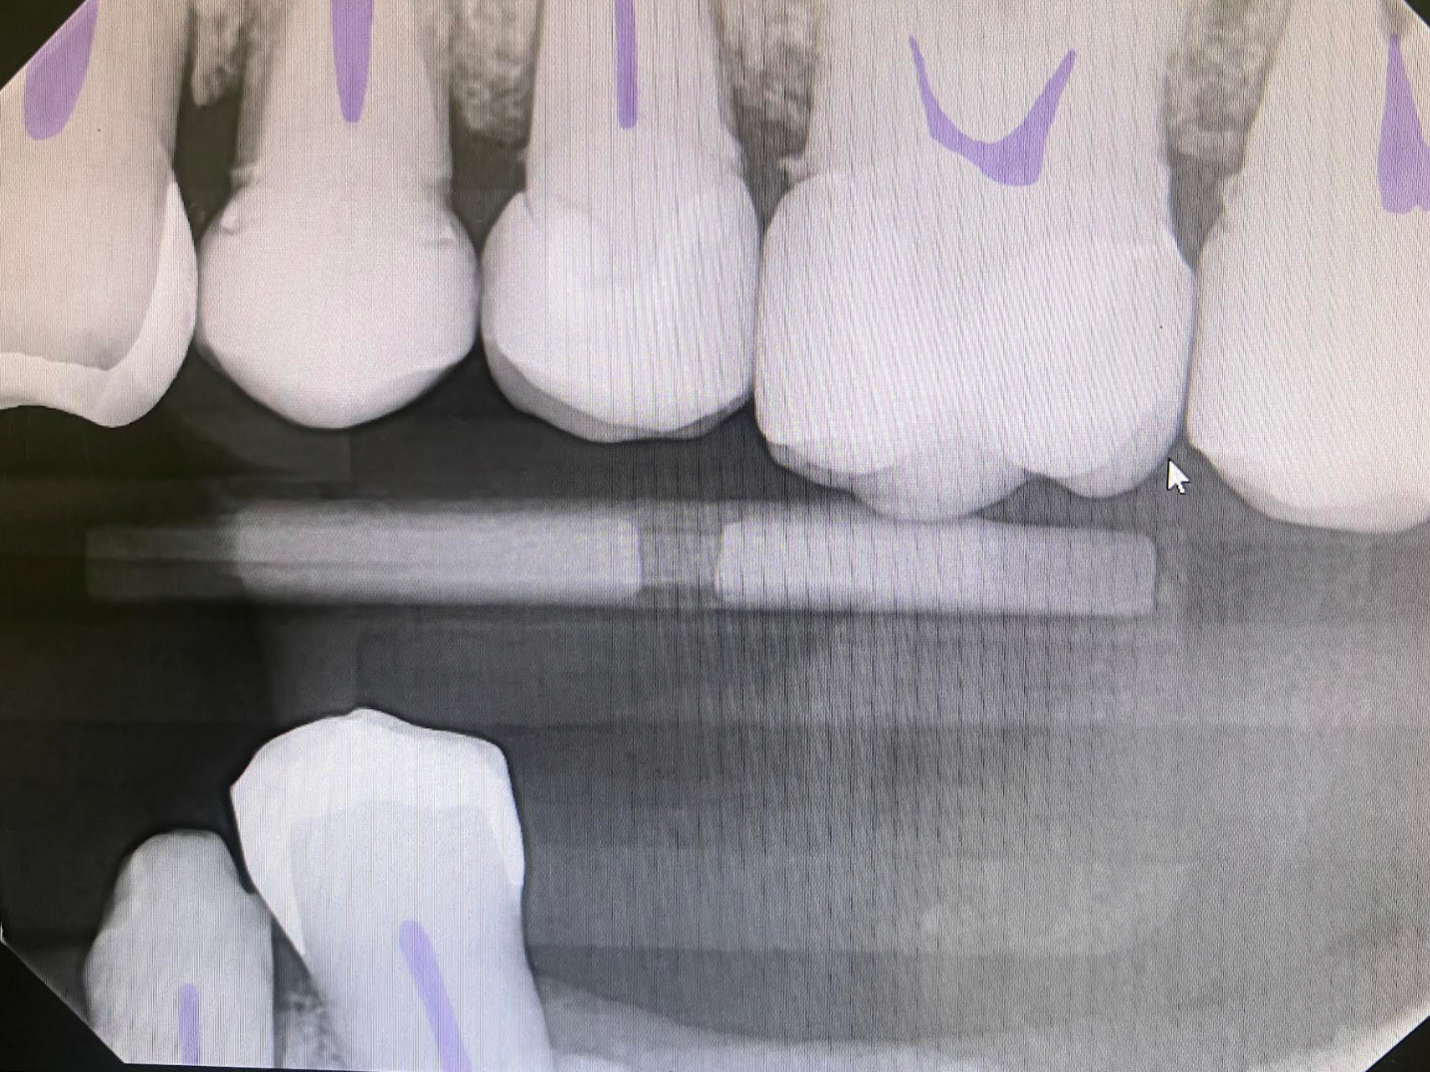

Example 2: Helping with training a hygienist

In this simple example we have a patient with restorative and periodontal needs. For a newer hygienist several things can be missed here that are made much more straightforward with Overjet:

Whereas a more inexperienced hygienist or associate might focus on the fact that the patient is missing a crown on tooth #21 and just mention that, with Overjet the full picture is seen:

And with the help of Overjet the patient has already had the discussion of the need for SRP, recurrent decay under crown #12, as well as the need for a crown on #21 ensuring simple dental work is not missed and also is easily shown to the patient. It is also listed for the hygienist to clearly see so they can start learning to identify subgingivial calculus, bone loss, and recurrent decay. It is also used against insurance company denial: